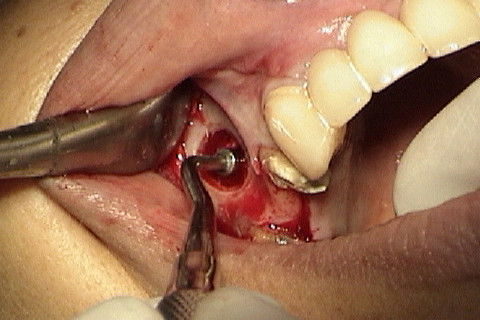

Abertura do retalho e inicio da remoção dos parafusos de osteossíntese na região 12

Abertura do retalho e inicio da remoção dos parafusos de osteossíntese na região 22

Marcação atraves do guia cirúrgico das posições dos implantes

Colocação dos implantes nas regiões 12 e 22 e perfuração das regiões 11 e 21